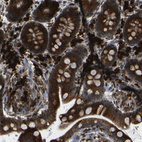

Immunohistochemical staining of human Epididymis shows strong cytoplasmic positivity in glandular cells.